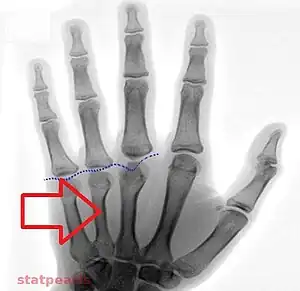

| Short 3rd to 5th metatarsals as may be seen in pseudohypoparathyroidism type 1a and 1c | |

Type 1a Pseudohypoparathyroidism is clinically manifest by bone resorption with blunting of the fourth and fifth knuckles of the hand, most notable when the dorsum of the hand is viewed in closed fist position. This presentation is known as 'knuckle knuckle dimple dimple' sign (Archibald's sign). This is as opposed to Turner syndrome which is characterized by blunting of only the fourth knuckle, and Down syndrome, which is associated with a hypoplastic middle phalanx.

- Has a characteristic phenotypic appearance (Albright's hereditary osteodystrophy), including short fourth and fifth metacarpals and a rounded facies. It is most likely an autosomal dominant disorder.[9] It is also associated with thyroid stimulating hormone resistance. Caused by GNAS1 mutation.[10]